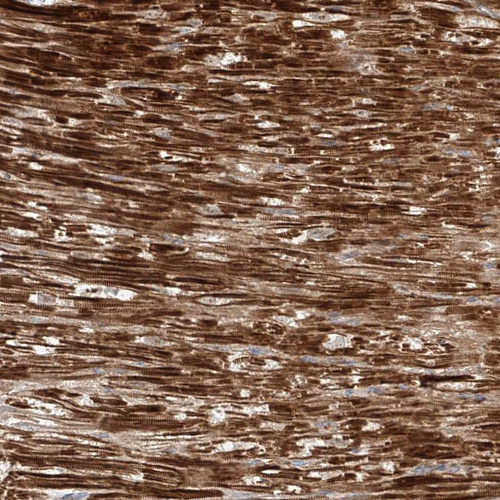

Immunohistochemical staining of human heart muscle shows strong cytoplasmic positivity in cardiomyocytes.